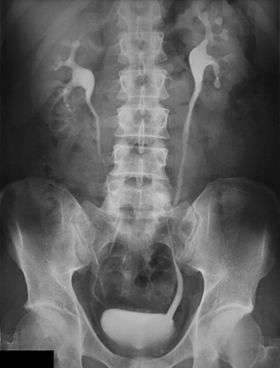

Diagnosis may include a fluorescence in situ hybridization (FISH) test, computed tomography urography (CTU), magnetic resonance urography (MRU), intravenous pyelography (IVP) x-ray, ureteroscopy,[6] or biopsy.